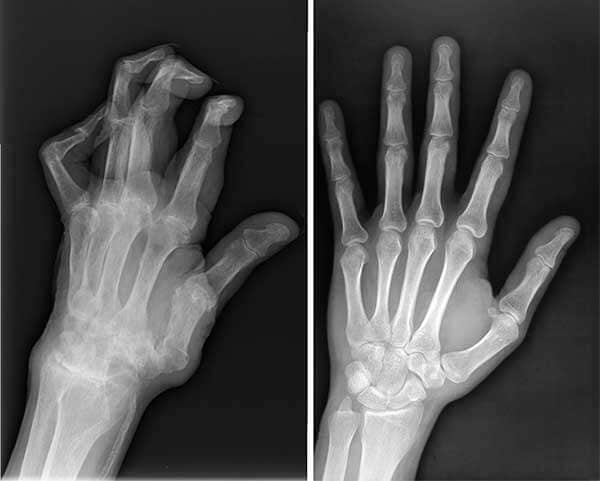

Incluso mi esposo, Carlos, padecía artritis en los dedos. Sus manos se deformaban y a veces el dolor era insoportable. No podía ni sostener una taza de café. Le di Flexacil, y ahora vive sin dolor. Se nota la mejoría en la movilidad de sus dedos.

Radiografías de las manos de Carlos, antes y después de Flexacil.

Se nota la mejoría en la movilidad de sus dedos.